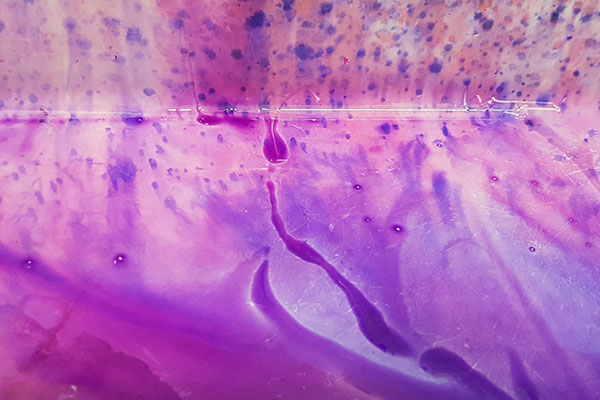

Waters of Pathology

Gink Yang

Future Industries Institute

Pathological assessment of biological samples often requires the use of Haematoxylin and Eosin (H&E) staining. My own research, nonetheless requires this simple procedure to assess the severity and progression of tumours and wounds. This simple yet crucial experimental process is often overshadowed by other complicated procedures. Here, the elegant and velvety watercolours of H&E is captured as the experimental procedures are being carried out. The image itself represents the unsung heroes in our scientific world

as well as in our society.